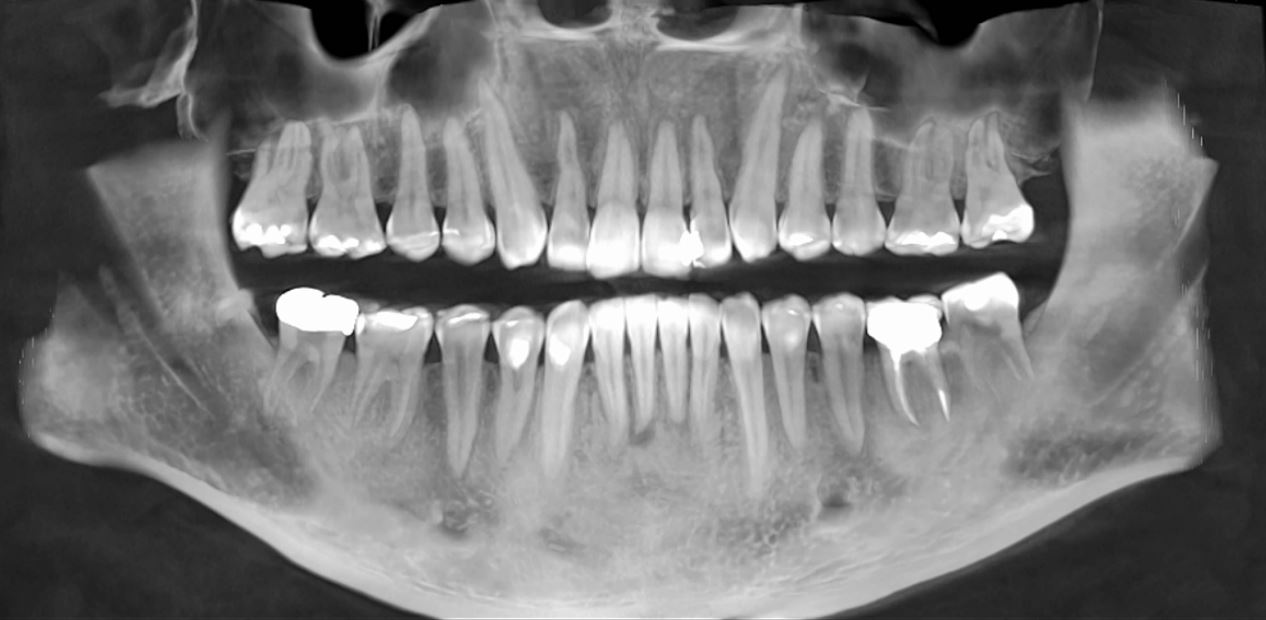

3D Imaging & Digital X-Rays

Advanced Digial X-Rays and 3D Dental Imaging Technology

What is CBCT (3D) Imaging Used For?

3D Imaging can be used in a variety of dental procedures, including:

• Dental Implant Placement

• Root Canal Therapy

• Surgery Planning

• Examine the Quality of the Bone Tissue

• Prosthetic Devices

• Disease Diagnosis

• Overdenture

• TMJ Treatment

• Tooth Extractions

We use the best 3D Cone Beam by Planmeca which provides:

Our Planmeca CBCT imaging unit complies with a multitude of diagnostic requirements and provides volumes sizes for every clinical application

We offer CT Scans for our dental patients or as an imaging center for outside patients

Its equipped with a Movement Correction Algorithm

It has a Dedicated Endodontic Imaging mode

Planmeca Ultra Low Doseā„¢ is the leading and scientifically proven method for acquiring CBCT images at a low patient dose

Our Cone Beam offers a seamless imaging workflow and relaxing patient experience due to its open patient positioning

How long is a 3D Dental Scan?

We have the latest technology in 3D imaging and our Planmeca 3D ProMax Cone Beam only takes 15 seconds to take the image once the patient is in place!

Is 3D Imaging Safe for me?

Our Dental Cone Beam CT machines emits less radiation than any other traditional CT scan & traditional film X-Rays.

The exposure is brief & minimal. Pregnant women should inform the dentist of their situation before getting a 3D X-Ray or X-Rays of any kind.

Digital Dental X-Rays

We use the advanced Nomad Pro 2, a handheld X-Ray Unit by Kavo, which is a leading brand in dental technology!

Images are crisp clean, the patient does not experience the gag feeling like the traditional X-Rays do